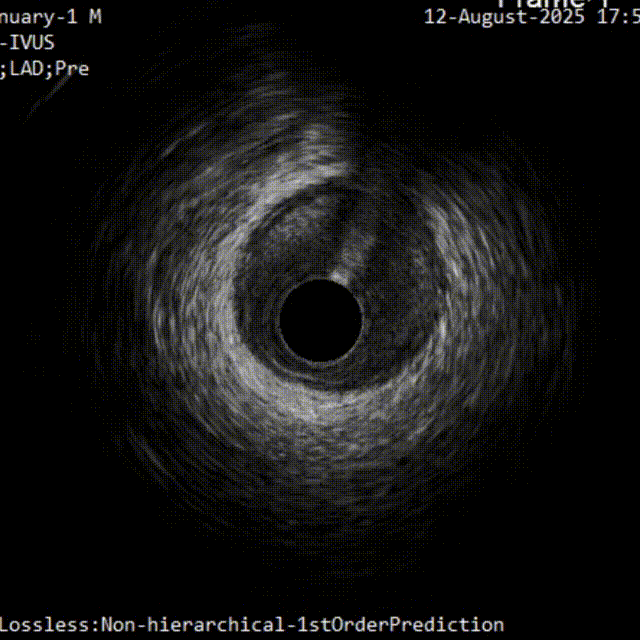

首先进行正向准备,对角支回撤IVUS明确CTO入口,Pilot200导丝进入

IVUS证实导丝进入CTO入口正确